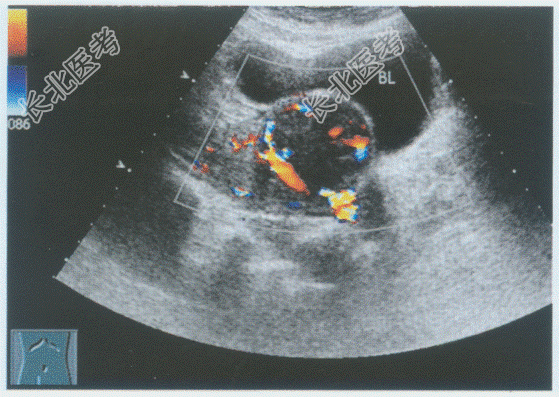

- 单项选择题临床资料:女性, 40岁,常规体检。超声综合描述: 子宫前位,宫底右前壁可见5.0cm×4.6cm稍低回声区, 边界清晰,形态规则, 内回声尚均匀,向包膜外突起, CDFI:稍低回声区内及周边可见丰富动静脉血流信号。见下图及彩图。其超声提示: